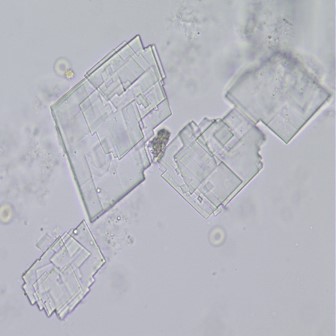

Match the image with the appropriate ID

A

B

WBC cast

Budding yeast

WBCs

RBCs

Transitional epithelial cell

Oval Fat Body

Uric Acid

Triple phosphate

Calcium carbonate

Bilirubin crystal

Granular cast

Cholesterol crystals

Leucine crystal

RBC cast

Waxy cast

Starch granule

Clue cells

Schistosoma haematobium

Renal tubular epithelial cells

Ammonium biurate